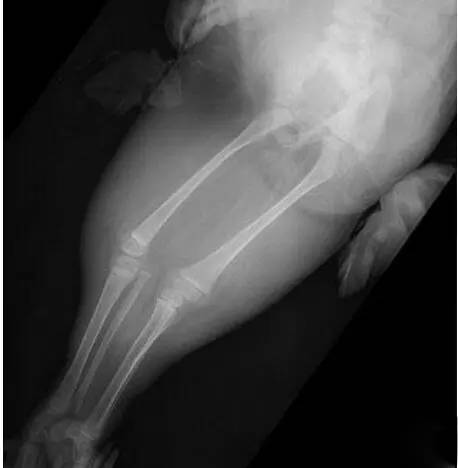

无独有偶,一位40岁的二胎妈妈在一次常规的产检中,发现胎儿下肢是两个大腿骨, 并行排列 ,小腿骨好像有点交叉 。医生介绍正常胎儿的下肢是不停地在妈妈肚子里动的, 呈现一个外八字,像这种情况,医生从医40年也是第一次见,后来确诊为美人鱼综合症。因为多数患病的新生儿出生后,只能存活几个小时,就算活下来,也要接受多次手术治疗。最终,在医院的帮助下,这位二胎妈妈选择了终止妊娠。

胎儿常见畸形检查图

(多发畸形)